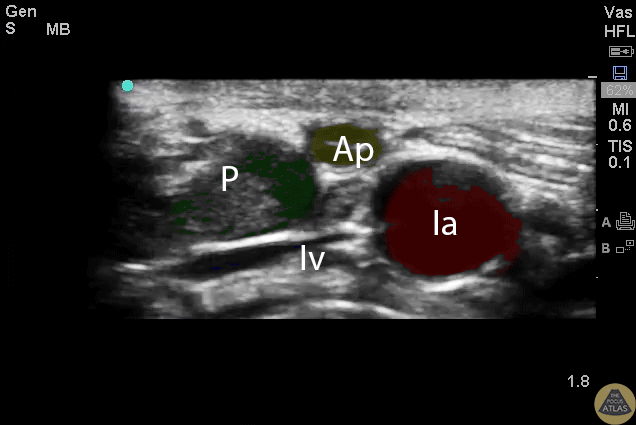

Colorized Appendicitis - Labeled Colorized Appendix with Landmarks

Normal appendix with landmarks highlighted. P=Psoas, Ap=Appendix, Ia=Iliac Artery, Iv=Iliac Vein Images provided by Sathya Subramaniam - Children’s Hospital of Philadelphia, edited by Matthew Riscinti - Kings County Emergency Medicine